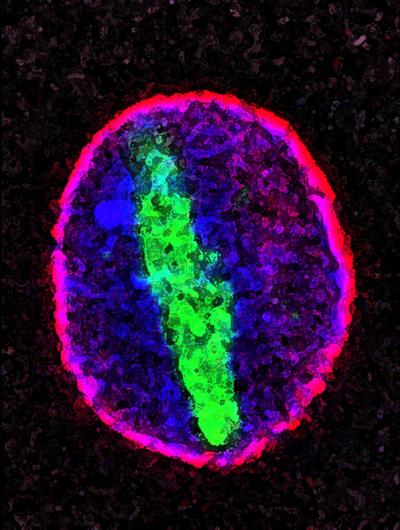

What they found was that in aging cells, one of the proteins composing the scaffold structure becomes damaged, and the permeability barrier deteriorates; molecules that should be restricted to the cytoplasm invade the nucleus.

In particular, a protein called tubulin, which is strictly a cytoplasmic protein, shows up as long filaments that co-opt a large part of the nucleus. For more than 100 years, pathologists had been aware of these filaments, but their origins were unknown. Associated with several neurodegenerative diseases, including Parkinson's, the filaments are found particularly in the substantia nigra of many Parkinson's patients, the part of the brain that is involved in dopamine production and that is affected by the condition.

Hetzer's team hypothesizes that it is the age-dependent defects in the scaffold proteins that undermine the nuclear permeability barrier. "We predict that when the permeability barrier is impaired, molecules are either lost from the nucleus or can leak into the nucleus and thereby change gene expression profiles," says Hetzer. "This could be a general aging mechanism, and it provides an explanation for the origin of these filaments, which have been known by pathologists for a long time."